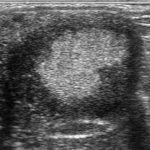

Ultrasound Examples of the Normal and Abnormal Ovulation

Ultrasound of the Normal and Abnormal Ovulation in the Mare

- A video PowerPoint presentation with description and discussion showing ultrasounds of normal and...